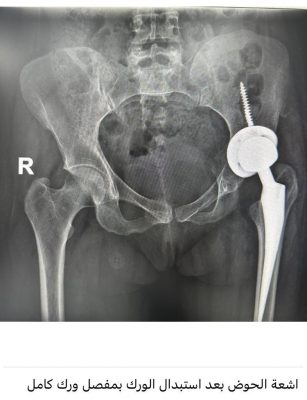

مضيفاً : وصلت المريضة للمستشفى وتم إجراء كافة التحاليل والفحوصات والإشاعات المطلوبة و التي أكدت إمكانية إجراء عملية تغيير مفصل كامل للورك بأمان رغم صعوبة التغيرات العظمية للورك وضمور العضلات وقصر الرجل وتمت العملية بنجاح ولله الحمد لتضاف للجراحات النوعية في جراحة استبدال مفصل الورك التي تتم في المستشفى ،وتؤكد على تطور الخبرات الطبية بالمستشفى بأحدث التقنيات الطبية الحديثة المتطورة عالمياً.

واختتم العتيبي حديثه مشيراً إلى أن المريضة بدأت في مرحلة التأهيل لاستعادة الحركة بدون ألم بمفصل ورك صناعي كامل.